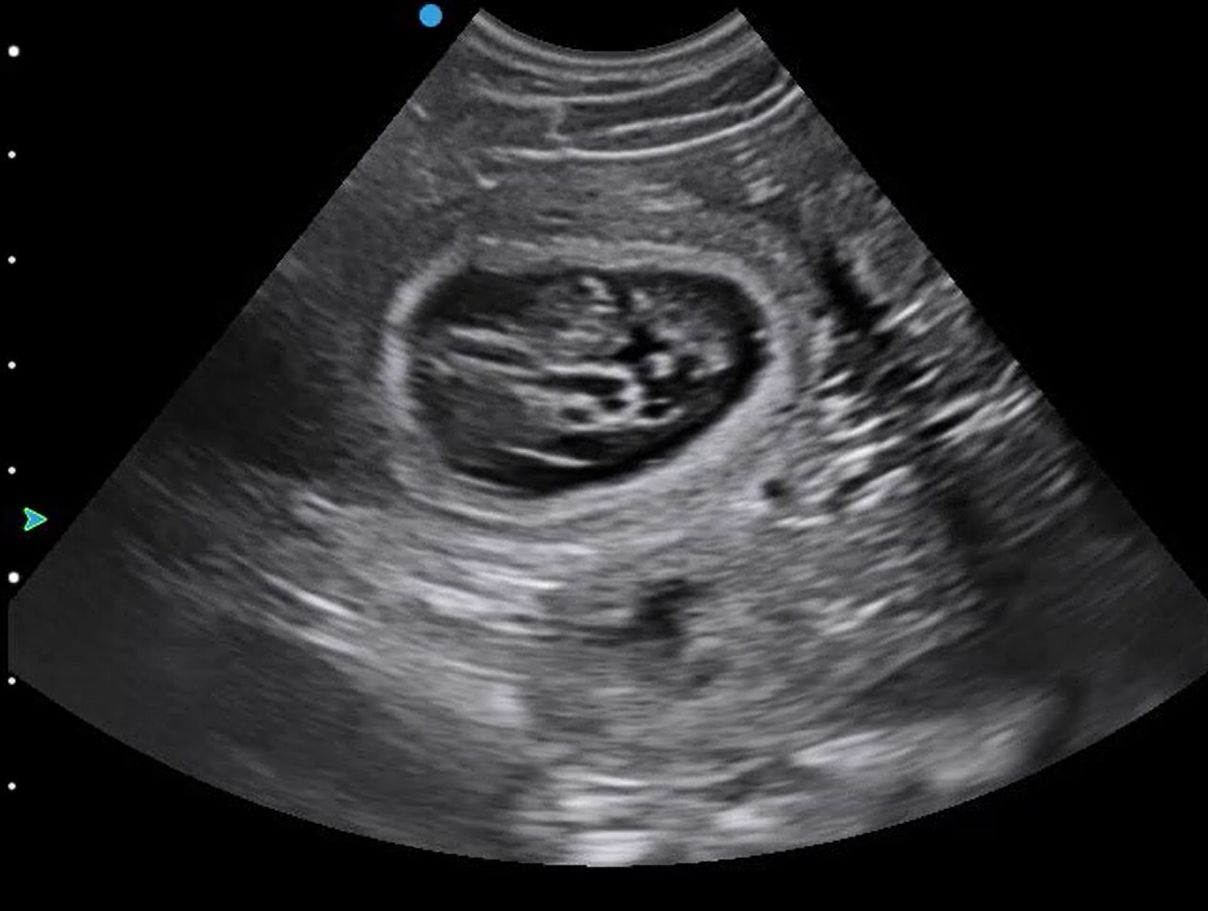

I was lucky enough to scan a beautiful Stabyhoun today, at around 31 days pregnant. It is very difficult (and inadvisable) to estimate numbers with ultrasound, but we definitely saw four sacs altogether in a single shot, and quite possibly 3 separate ones closer to the bladder, so a safe number estimate would be anywhere from six upwards!

All the gestation sacs looked very healthy, with strong heartbeats seen in several puppies. It was also possible to obtain an umbilical Doppler trace.